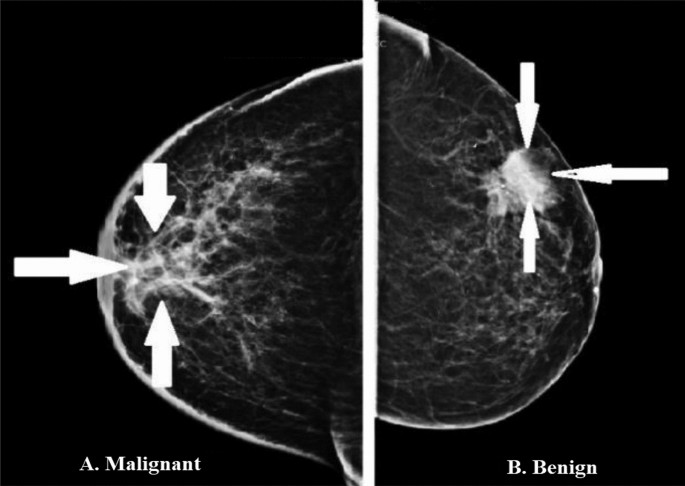

For our data, we will use the breast cancer dataset from scikit-learn. This dataset contains tumor observations and corresponding labels for whether the tumor was malignant or benign.